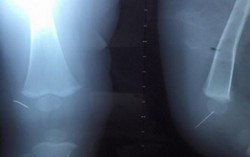

20 năm đau khớp gối, nữ bệnh nhân thoát cảnh phải bò nhờ phẫu thuật

14:11 22/04/2019Bệnh nhân bị thoái hóa khớp giai đoạn cuối biến dạng nặng, mỗi khi di chuyển rất khó khăn thậm chí phải bò. Tuy nhiên, bệnh nhân đã được bác sĩ phẫu thuật và đi lại bình thường.